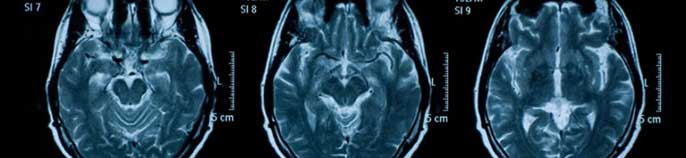

The gift also supports UCSF’s preeminent neuroscience enterprise, including its Sandler Neurosciences Center and neurology programs at Mission Bay.

The center, a five-story, 237,000-square-foot building that opened in 2012, brings under one roof several of the world’s leading clinical and basic research programs in a collaborative environment. UCSF’s neurology and aging efforts are focused on finding new diagnostics, treatments, and cures for a number of intractable disorders, including Alzheimer’s disease, Parkinson’s disease, multiple sclerosis, stroke, migraine, epilepsy and autism. The programs also seek to integrate neuroscience and clinical disciplines with public health initiatives in order to disseminate and implement novel findings from research centers of excellence, as well as conduct community outreach to raise awareness about the diseases of aging.